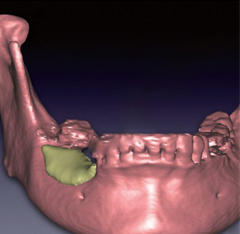

数字化种植是利用计算机图形图像技术,根据口内CT扫描数据以及光学扫描数据在计算机上重建患者颌骨立体模型,医生以此为基础,确定患者种植体嵌入位置、数量、种植深度、角度等,生成科学、精准的导板设计方案,将种植设计准确地转化到手术操作中,最后配上数字化种牙手术专用的手术工具、结合患者自身的情况制作修复体,完成种植治疗。

- 口内模拟种植,避开神经血管,设计种植方案;通过CAD/CAM激光扫描和CBCT检测等, 在计算机上重建患者口腔三维立体模型,凭借由打印技术制作的种植导板对手术全程的精准把控,减少手术时间及手术创伤,实现对缺牙的修复。

- 利用数字化技术,术前充分评估患者条件,设计合适的种植体数量、型号和具体位置,保证负重的成功及植体稳定性,配合使用打印种植导板精确实现设计的种植方案,同时缩短手术时间,减少手术创伤,让患者有更好的体验。